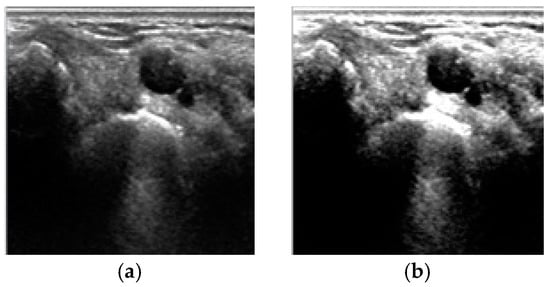

4. Results and Discussion